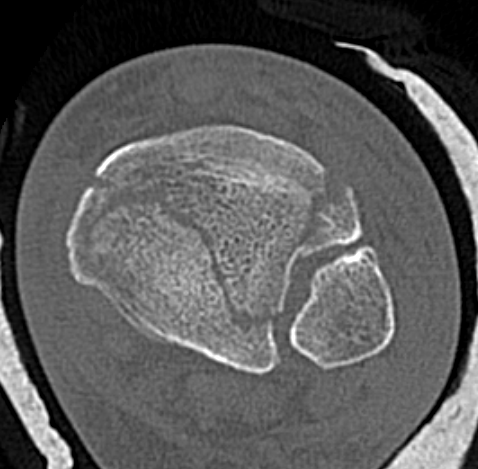

Commonly 3 fracture configurations

- medial malleolus

- posterolateral fragment / Volkmann

- anterolateral fragment / Chaput

Tibial plafond common fragmentsTibial plafond fragments